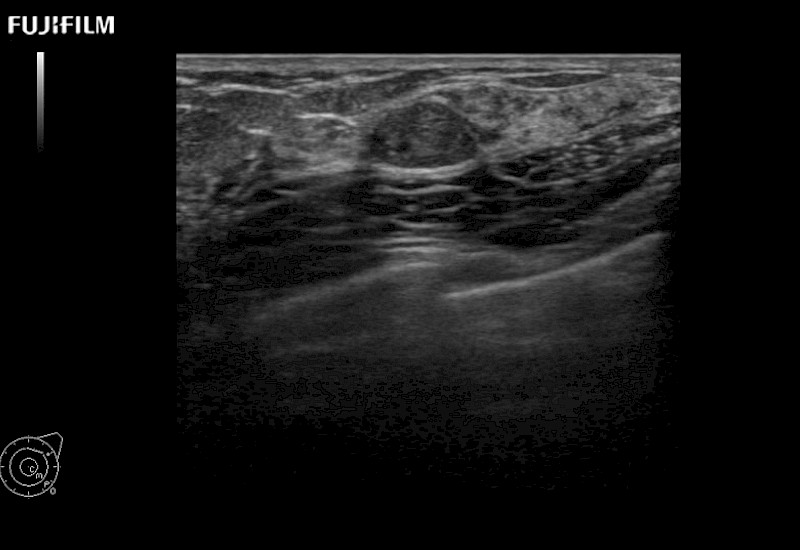

for use during open and laparoscopic procedures: Tumor localization & staging, Ablation, Resection, Biopsy, Transplant, Abdominal exploration, Robotic surgery

Our dedication to Surgical Oncology allows us to offer superior image quality, outstanding system reliability and intuitive use of cutting edge technology.

Learn moreFujifilm Healthcare continues to listen to the experts, our neurosurgeons, by developing an ultrasound system specifically designed for the Operating Room.

Guidance is the fundamental purpose for all of our surgical ultrasound technology. Fujifilm Healthcare is committed to designing tools that help neurosurgeons navigate inside the human body and provide the necessary information to immediately make critical surgical decisions.

With the ARIETTA Precision the next level of surgical ultrasound is here.